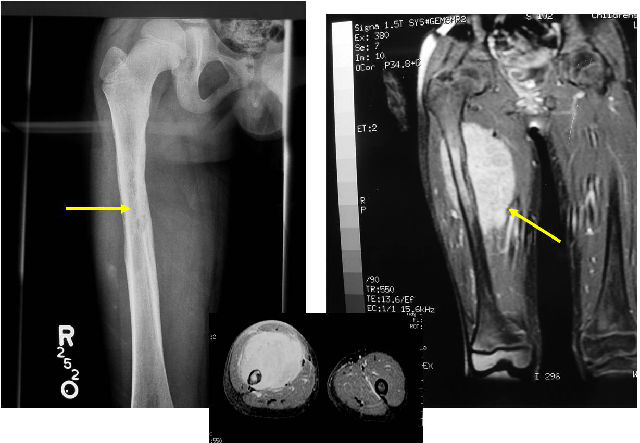

2010年1月,我开始发现自己右侧股骨不对劲,伴有疼痛感,就医后经过一系列检查最终被确诊为骨外尤文肉瘤/原始神经外胚层瘤,接受了右大腿病灶手术切除以及6个疗程的辅助化疗。然而2014年,左胫骨也不幸出现了破坏性病灶,肿瘤复发,4年多的奔波就医,早已让我和我的家人疲惫不堪。我才16岁啊,未来的路还很长,我该怎么“走”下去……

选择好医友

2015年2月,在我的左胫排骨MRI扫描中,发现破坏性病变和异常软组织信号影,病灶周围骨质及软组织水肿,并见区域性坏死灶,影像诊断可能为转移瘤。这对于我和家人而言无疑是当头棒喝,寻求更先进的医疗技术和更好的治疗方案成为了当务之急。在一个朋友的介绍下,我们知道了“好医友”国际医疗平台,在进行了相关了解之后,便与他们取得了联系,希望能通过这个平台和美国相关专科医生进行远程视频会诊。

鉴于免疫组织化学标志和我的年龄,阿伦·辛格医生认为尤文肉瘤/原始神经外胚层瘤的诊断看似正确的,虽然核磁共振扫描显示我左胫骨有新病灶,但这个病灶之前的活检尚无定论,就这个病灶的大小,MRI影像的特点以及FDG活动性病变,他认为转移性尤文肉瘤/原始神经外胚层瘤,具有临床意义。